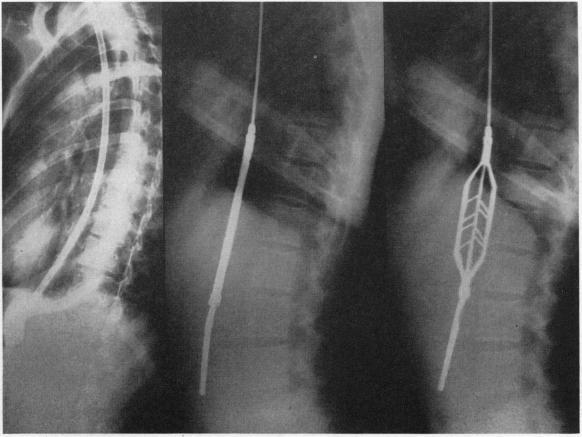

MANAGEMENT OF CARDIOSPASM.

Calif Med. 1947 Jul;67(1):23-8.